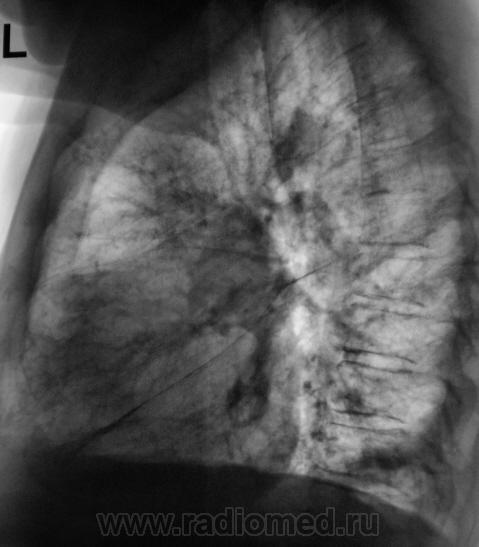

Произведены томограммы.

Здравствуйте Almo! Томограммы выполнены в стандартных срезах - 7, 9, 11 см.

Эта штучка неотделима от правой промежуточной артерии...

На "томо" шикарно видно:

1. Гиповентиляцию правого лёгкого.